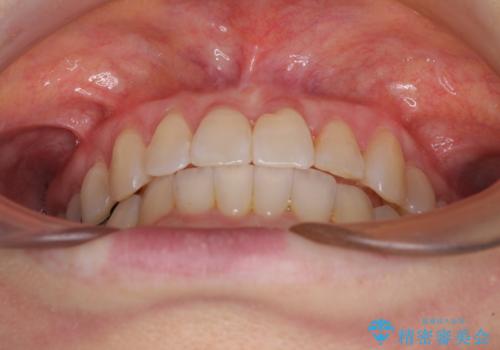

前歯のクロスバイト インビザライン矯正で改善

- むし歯治療を契機に、長年気にしていた前歯のクロスバイトの改善を希望された患者様です。

汚れが溜まりやすく、歯ぎしりがうまくできないため、インビザラインを用いて矯正治療を行うこととしました。

インビザラインによる前歯のクロスバイトの改善は、治療期間中に前歯でしか咬めない時期が続いたり、歯肉退縮や歯髄壊死のリスクが高まったりと、治療中にトラブルを抱えることがあります。

特に上顎側切歯(真ん中から2番目の歯)が舌側に引っ込んでいるケースは、インビザラインでは改善しきれないことがあると言われています。